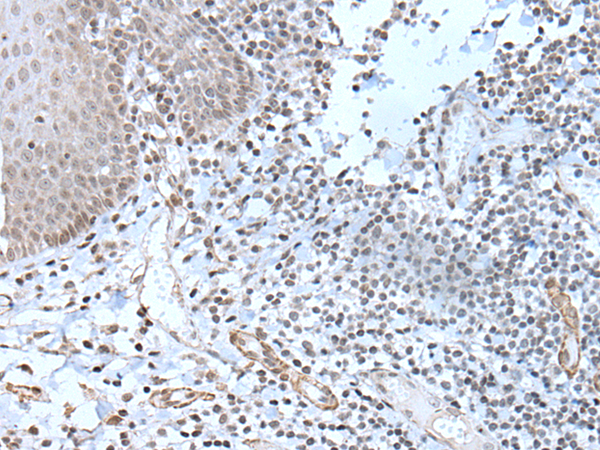

IHC positive control: